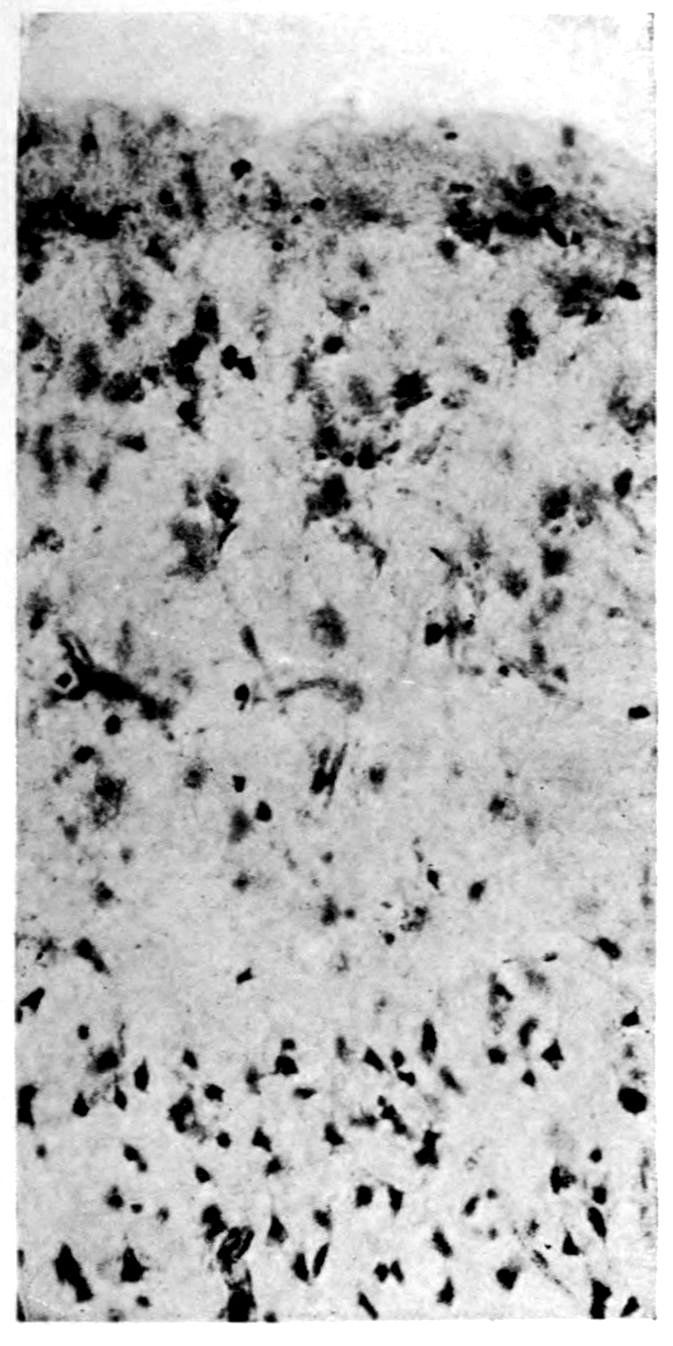

A. Normal postcentral cortex. (Compare B.)

B. Nerve cell losses. Perivascular deposits of mononuclear cells, amongst which are numerous plasma cells. Note decrease in number of nerve cells. Note irregular disposition of nerve cells. From paretic neurosyphilis.

Microscopic findings are here presented merely in sufficient detail to establish the diagnosis. The left superior frontal gyrus shows extensive and somewhat irregular cellular and fibrillar gliosis of the plexiform layer, together with an increase of thickened vessels having lymphocytes and plasma cells in their sheaths.

The perivascular infiltrations are most extensive in the lower layers of the cortex. The lamination is in places thoroughly obscured, except that representatives of the layer of large external pyramids are almost always demonstrable.

The layer of medium-sized pyramids has undergone more numerical loss of elements than have the other layers.

Gliosis of white matter.